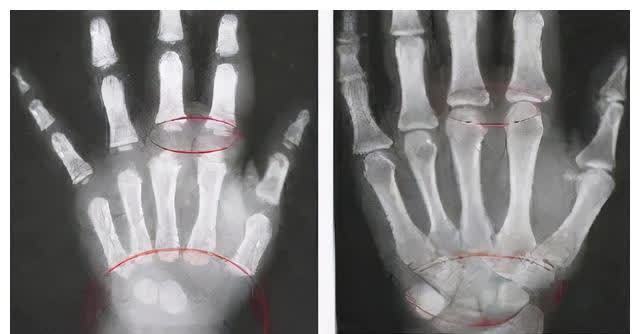

判断孩子的生长水平需要通过骨龄来判断孩子是不是晚长要通过看骨龄片、评估骨龄来确定的。

骨龄偏大一岁代表孩子少长一年

这时候可以通过延缓骨龄、拉长生长周期来做身高管理如果孩子骨龄偏小一岁代表骨骼闭合的时间会晚一年长高的空间会大一些但要注意

如果孩子骨龄偏小较多可能存在营养不良、生长激素缺乏、发育迟缓等问题

依然是长不高的。

所以要具体问题具体分析不是简单的看到孩子个子比同龄人矮就是晚长抱着再等等的态度。